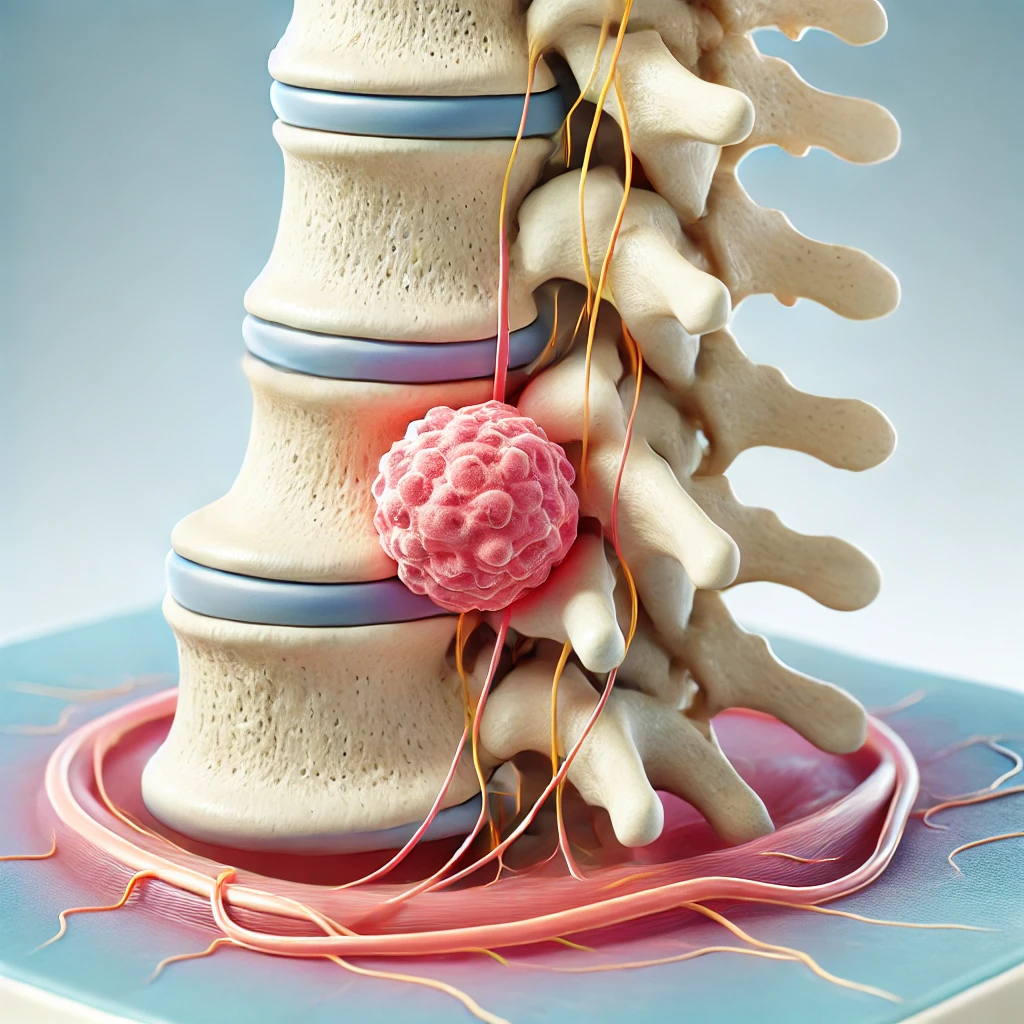

نغطي كل التخصصات الطبية

استیعاب کافة الحالات الطبیة لشمولیة التخصصات